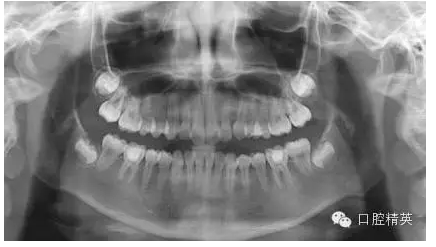

1,術(shù)前X-ray,常規(guī)術(shù)前攝片,

為患者和自己保留一份客觀記錄。。。